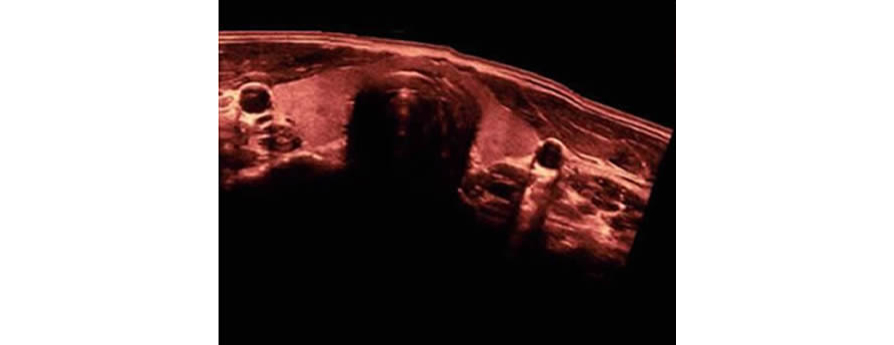

Obtenga una vista completa y ampliada de la estructura anatÃģmica con imÃĄgenes panorÃĄmicas que, junto con la indicaciÃģn de velocidad y la capacidad de exploraciÃģn hacia adelante/atrÃĄs, hacen que la exploraciÃģn sea mucho mÃĄs fÃĄcil, mÃĄs suave y mÃĄs controlable.

Obtenga una mejor informaciÃģn de diagnÃģstico a travÃĐs de una vista ampliada de la estructura anatÃģmica en todas las sondas convexas y lineales.